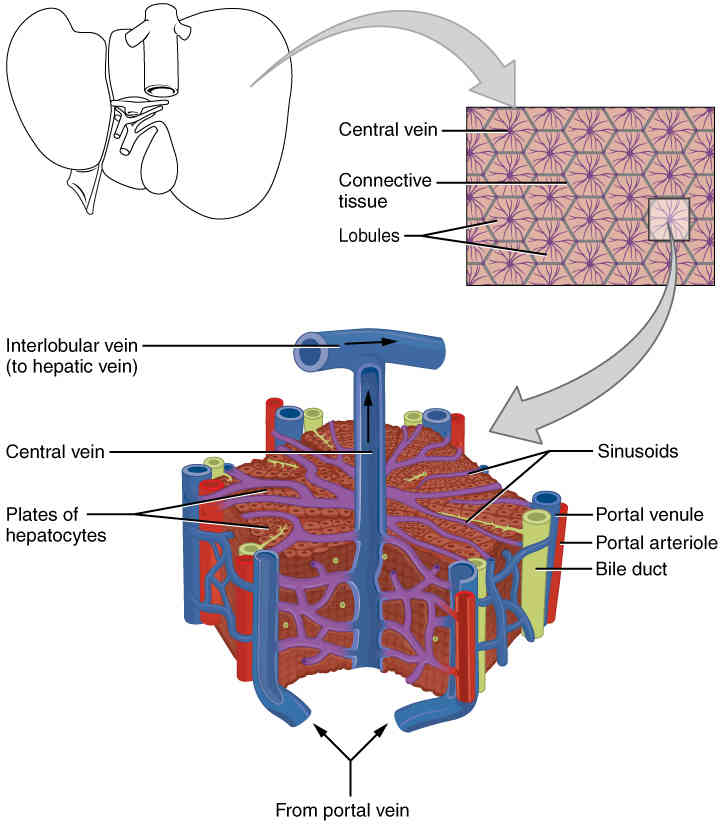

This page is under construction. For now, it is just a resource of the images found in the OpenStax Anatomy and Physiology Handbook. It wil slowly change into a revision tool. Each slide has a number. Use this to refer to the slide. When completed, it will have an unlabelled section, with labelled slides in parallel. On the unlabelled slides, write your answer and use the labelled slide to assess yourself. Keep track by also noting the number on each slide. Improvement at each attempt is important, more so than full marks on a first attempt.